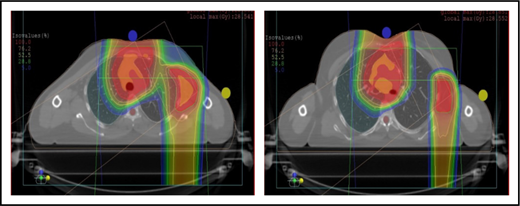

Proton therapy can significantly reduce the radiation dose to the breasts by specifically using fields that enter posteriorly and stop short of exiting through the breast. Alternatively, if protons cannot be used, other methods of displacing the breast can be used instead, such as using an inclined board or physically moving the breast out the beam path. Figure 3A shows how using proton therapy can spare the breast in a case with axillary involvement.

Axillary involvement at presentation. (A) Axial, coronal, and sagittal views of a proton plan (left) and an IMRT plan (right) for a patient presenting with axillary involvement. Use of proton therapy in this case spares the left breast. (B) Regardless of which treatment modality is chosen, IMRT (left panel) and proton (right panel), limiting the volume exposed to radiation should include attention to avoiding a low-dose bath. (C) Limiting lung dose. If avoiding the lung is the primary objective in a given patient, especially if the patient has received pulmonary toxic chemotherapy (eg, any combination of bleomycin, busulfan, gemcitabine, brentuximab, etc.), proton therapy may better spare the lungs by reducing the low-dose bath seen with photons.

When hilar disease needs to be covered, the dose to the breasts can increase, and avoiding the breasts becomes difficult with either modality (proton or photon). The choice of treatment modality for such cases must consider the doses received by other critical structures, such as the heart and lungs, especially in previously and heavily treated patients. However, in considering how to best limit the volumes exposed to radiation, avoiding “low-dose baths” is equally important (ie, irradiation of large volumes with low doses), regardless of which modality is used (Figure 3B).

Consideration of lung dose

With the advent of CT-based planning for mediastinal lymphoma, the dose to the lungs can now be correlated with the risk for pneumonitis. Restrictions on lung dose are encouraged to be V5 < 55%, mean lung dose < 13.5 Gy, and V30 < 20%. These values are more attainable with the use of DIBH.38 Although a mean lung dose of 13.5 Gy has been associated with a lower risk for pneumonitis, it is advisable to aim for a lower dose, which is quite often attainable when strict constraints are used. For example, when IMRT is used, it is important to limit the beams to some variation of anteroposterior beams, avoiding lateral beams. If avoiding the lung is the primary objective for a given patient, especially if that patient has received pulmonary-toxic chemotherapy (eg, bleomycin, busulfan, gemcitabine, brentuximab), proton therapy may better spare the lungs by reducing the low-dose bath seen with photons (Figure 3C).